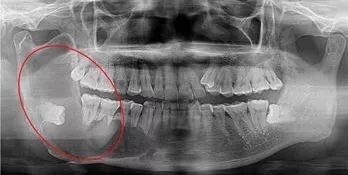

阻生牙(impacted teeth)是指部分萌出或完全不能萌出,且以后也不会自行萌出的牙。好发部位为下颌第三磨牙、上颌第三磨牙及上颌尖牙,其中阻生第三磨牙也叫做阻生智齿。

5、邻牙及支持组织的吸收:当阻生的智齿萌出过程中受阻于第二磨牙时,会引发第二磨牙牙根牙根逐渐吸收,严重者可使下颌第二磨牙远中牙根完全吸收,致第二磨牙松动、疼痛,常常食物嵌塞发生慢性牙周炎,也会造成牙槽骨的炎症性吸收,使第二磨牙反复肿痛。

7、智齿周围囊性病变:下颌阻生的智齿常常形成囊肿,引起骨头吸收。